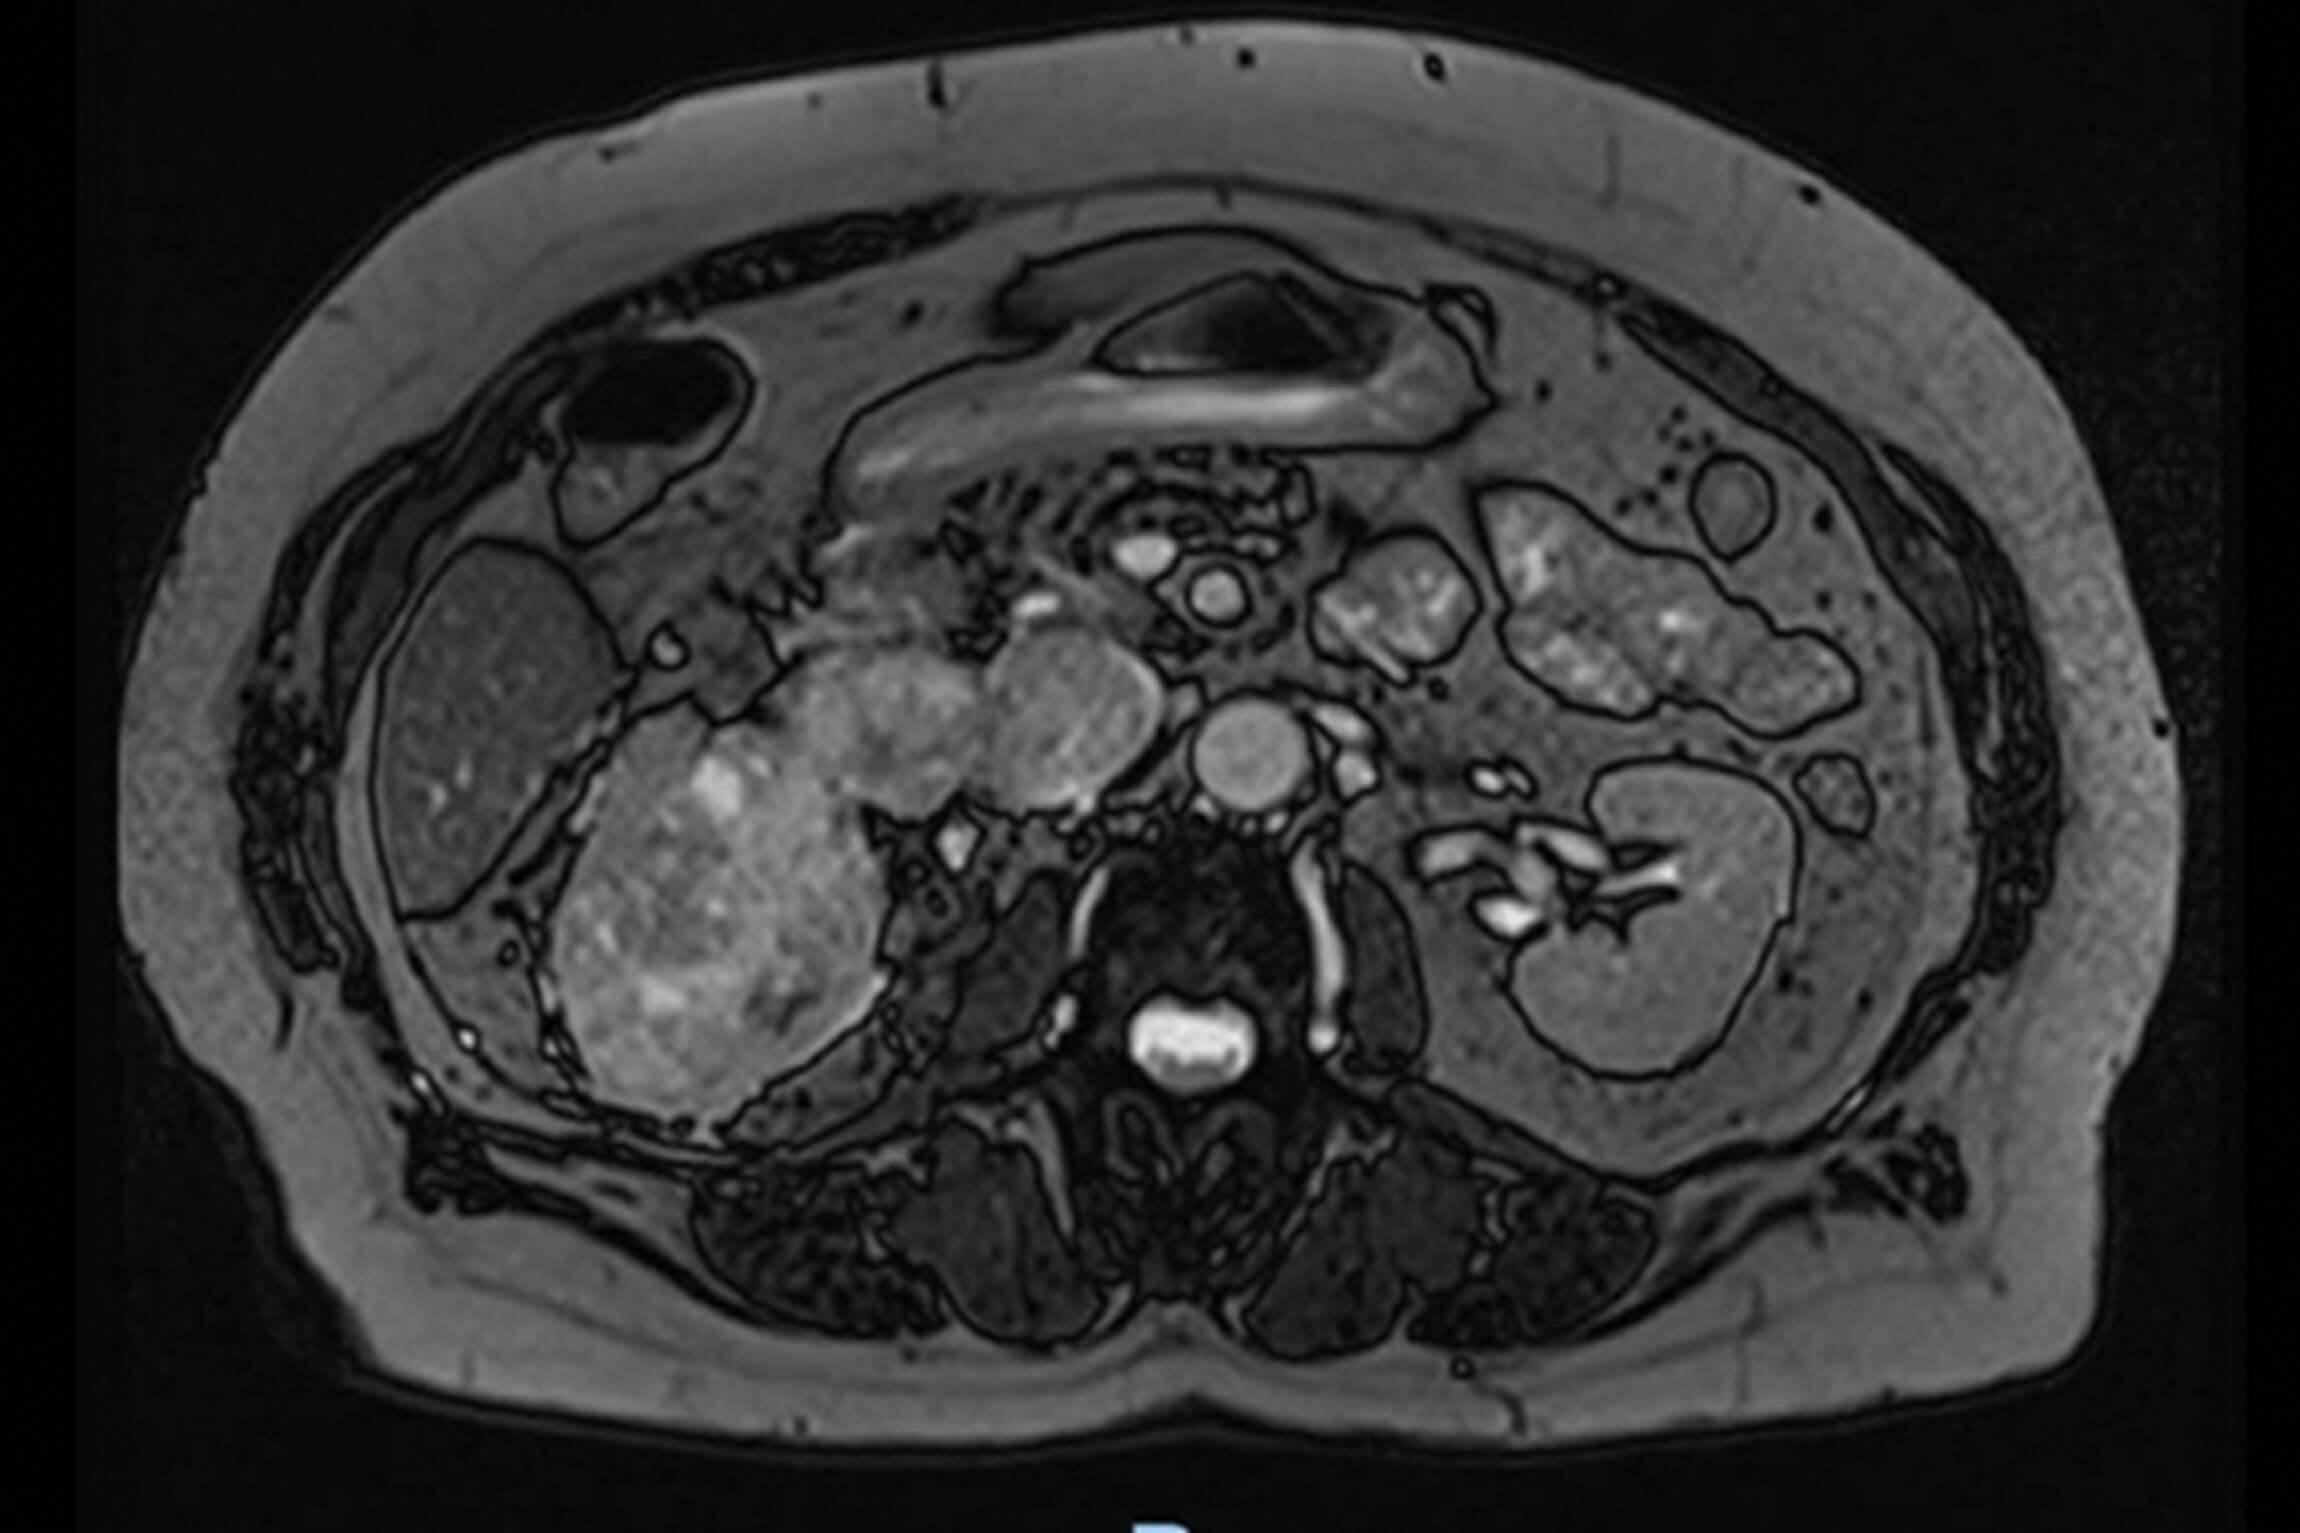

Figure 1.

1. This is an axial and coronal section of an MRI, which demonstrates a large right renal tumour. The tumour extends into the inferior vena cava but remains below the diaphragm. This patient therefore has T3bN0Mx disease. RCC staging follows the TNM staging outlined in article 1 ‘Localised Renal Cancer’.